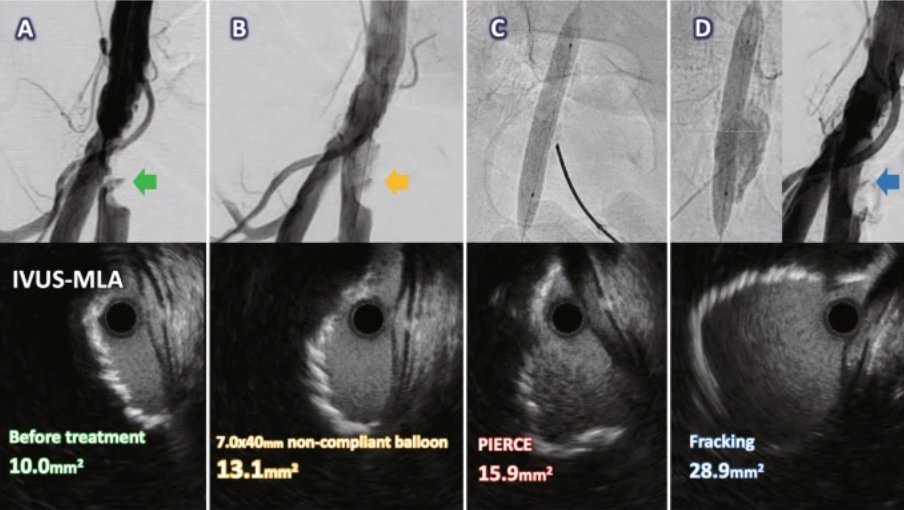

In this #NewTech🔬 classic, the authors described a novel approach to crack deep calcified plaque in the common femoral artery using hydraulic pressure: the fracking technique! Check it out again for free: cvirendovasc.springeropen.com/articles/10.11… #IRad #SundayRead

In this #NewTech🔬 classic, the authors described a novel approach to crack deep calcified plaque in the common femoral artery using hydraulic pressure: the fracking technique!

#AuthorSpotlight premiere! Dr. Haraguchi spoke to us about the popular article highlighting the "fracking" technique, used for cracking deep calcified plaque with hydraulic pressure youtu.be/Ze1eBWBDV6s Check out the original paper here for more tips: cvirendovasc.springeropen.com/articles/10.11…

Dr. Haraguchi spoke to us about the popular article highlighting the "fracking" technique, used for cracking deep calcified plaque with hydraulic pressure youtu.be/Ze1eBWBDV6s